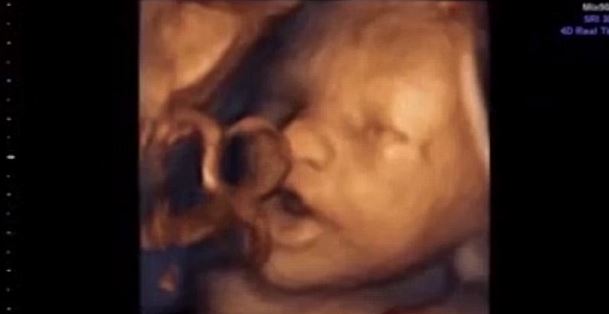

Απίστευτο βίντεο: Μωρό «τραγουδάει» μέσα στην κοιλιά της μητέρας του!

Τα αγέννητα μωρά είναι σε θέση να διακρίνουν ήχους μέσα στην μήτρα μετά από μόλις 16 εβδομάδες κύησης, σύμφωνα...